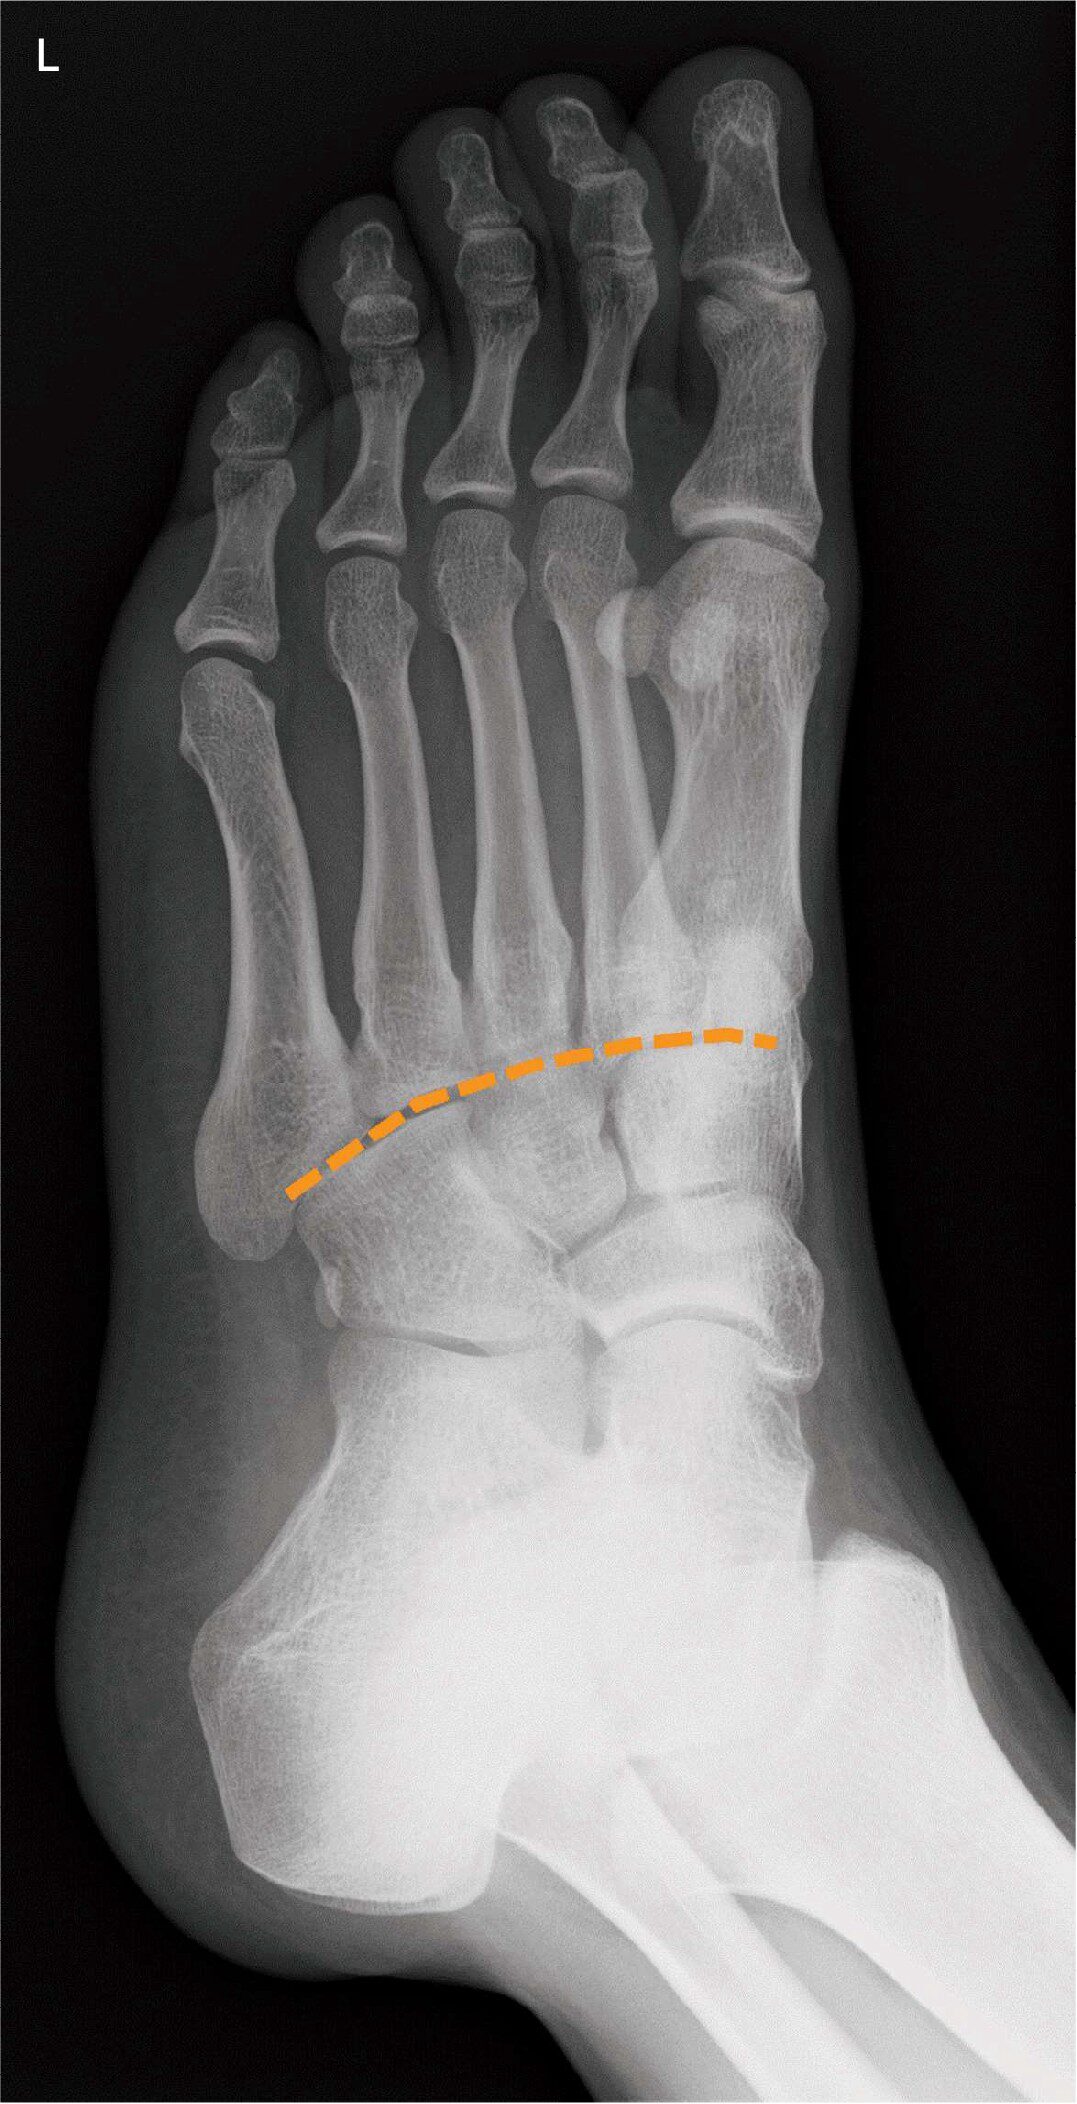

足部のX線写真(別冊No.9)を別に示す。破線で示すのはどれか。

- 1MP関節

- 2DIP関節

- 3PIP関節

- 4Chopart〈ショパール〉関節

- 5Lisfranc〈リスフラン〉関節